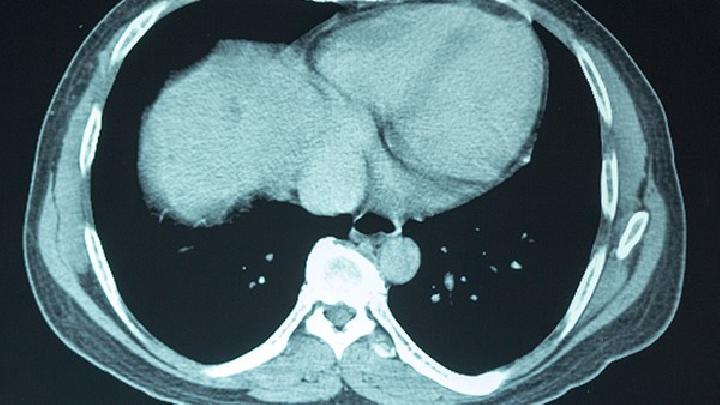

脑部CT检查诊断脑癌吗?脑部CT检查对脑瘤的检出率可达百分之九十以上,对病变大小、形态、数目、位置、密度和性质易于显示,且解剖关系明确,是目前脑瘤的主要诊断方法。下面看一下脑癌都有哪些检查方法?